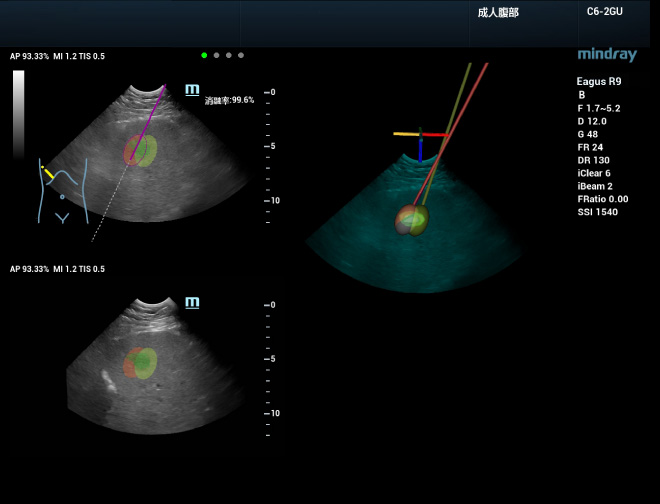

Llevar a cabo un tratamiento con mayor confianza

Durante la planificaciĂłn de la ablaciĂłn en 3D, se puede realizar una simulaciĂłn de la ablaciĂłn a fin de desarrollar una estrategia de tratamiento eficaz para lesiones grandes que deben extirparse con varias agujas. Primero, configure el rango de la ablaciĂłn para las agujas individuales y, luego, coloque las agujas para la ablaciĂłn en la simulaciĂłn. Se puede terminar de desarrollar un plan Ăłptimo observando la tasa de cobertura de la lesiĂłn en la pantalla en tiempo real. Este proceso es compatible con la visualizaciĂłn tridimensional en mĂșltiples ĂĄngulos, lo que permite una observaciĂłn intuitiva y multidimensional de la cobertura de la ablaciĂłn de todo el tumor. Luego, se puede guiar la aguja hacia el tumor real de acuerdo con la ruta planificada, y la cobertura de ablaciĂłn se actualizarĂĄ en tiempo real con la inserciĂłn real de la aguja. Con uHit Fusion, todo el proceso de ablaciĂłn se puede planificar y estandarizar mejor, lo que reduce la dependencia en la experiencia del operador.